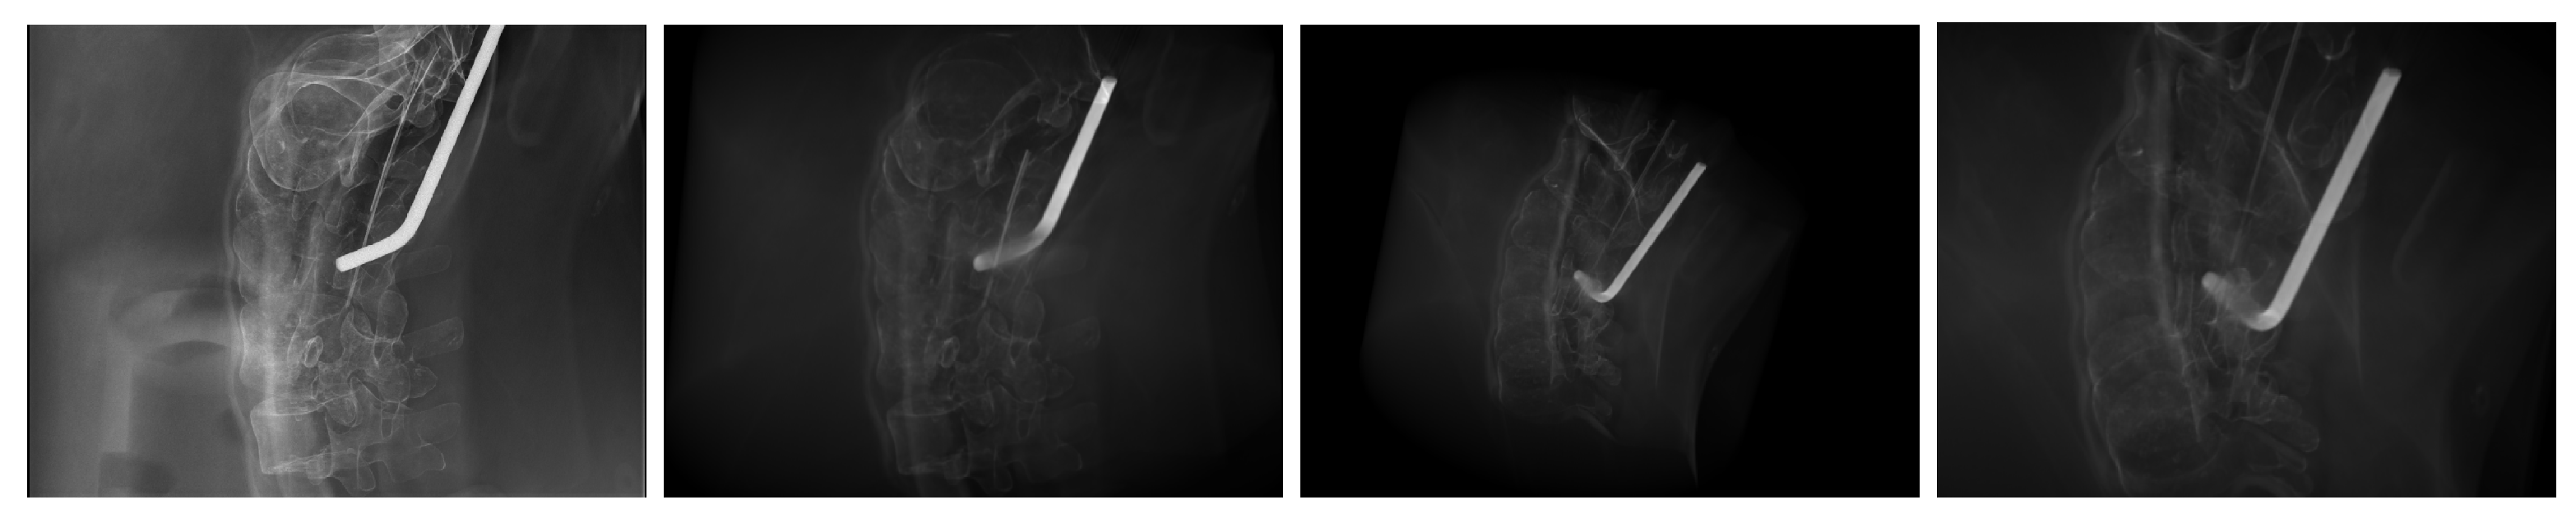

3. Results